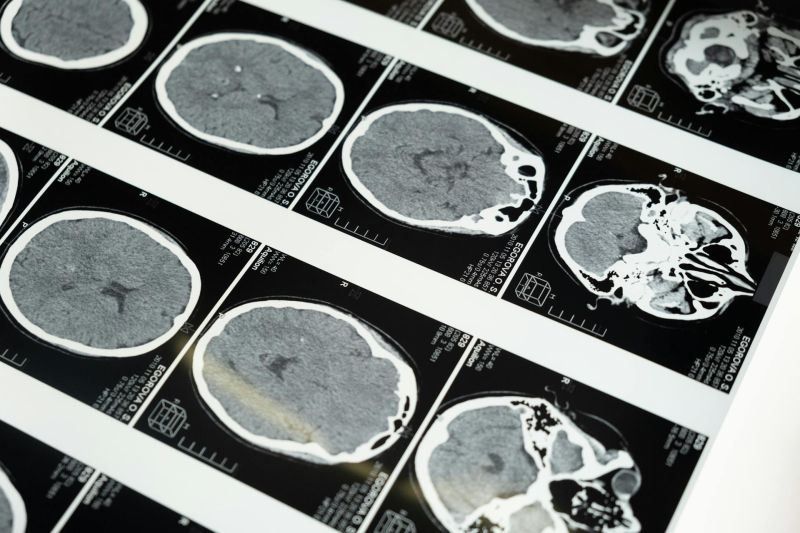

Multislajsni CT skener glave predstavlja rendgensku metodu snimanja kojom se dobijaju detaljni preseci mozga, lobanje, krvnih sudova i mekih tkiva glave. Ovim pregledom sagledavaju se promene koje se ne mogu jasno uočiti na običnom rendgenskom snimku, pa se lekarima omogućava brza i pouzdana procena stanja.

Pregledom mogu da se otkriju krvarenja, otoci, tumorske promene i druga strukturna oštećenja mozga i okolnih tkiva.

• Krvarenje unutar lobanje i nakupljanje tečnosti

• Posledice povreda mozga i kostiju lobanje

• Tumorske promene i prateći otok

• Promene krvnih sudova i poremećaji protoka krvi

• Strukturne nepravilnosti u građi mozga